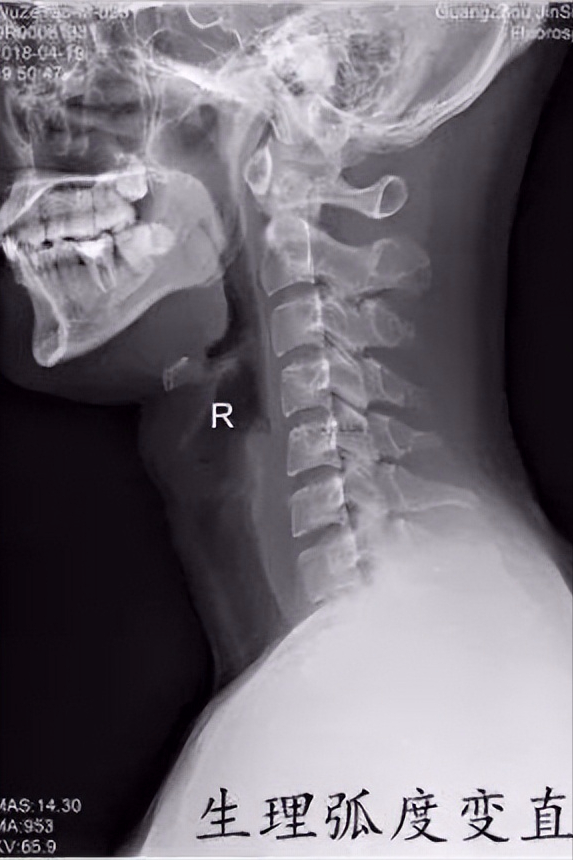

现在的年轻人大多长时间低头看电脑或则低头看手机,经常出现颈部疼痛、落枕、头晕头痛等不适,就诊拍片子经常能看到如下这些情况

这些片子提示你的颈椎的生理弯曲已经消失,甚至出现了反弓。为啥会出现这种情况呢?

其次为啥它会消失呢?主要是因为长时间的姿势不良导致的。低头时颈椎的生理弯曲会消失,长时间低头会导致肌肉过度紧张,导致身体前后肌肉力量不平衡,进而出现颈椎的生理弯曲消失。生理弯曲消失后,颈椎受力情况改变,小关节承受的压力增大,加剧退化;颈椎椎间盘受力增大,退化提前,可能导致椎间盘突出等情况发生。